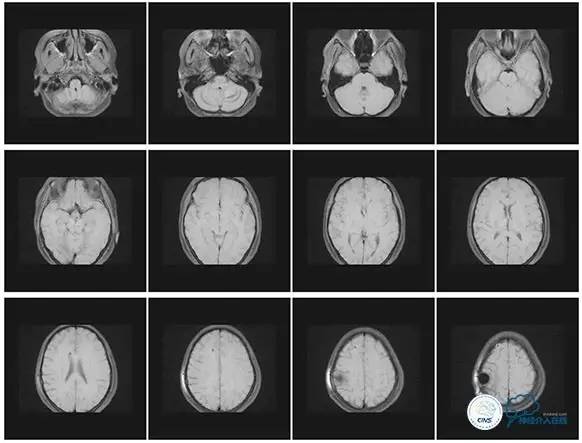

头颅CT

MRI T1

MRI T2

MRV